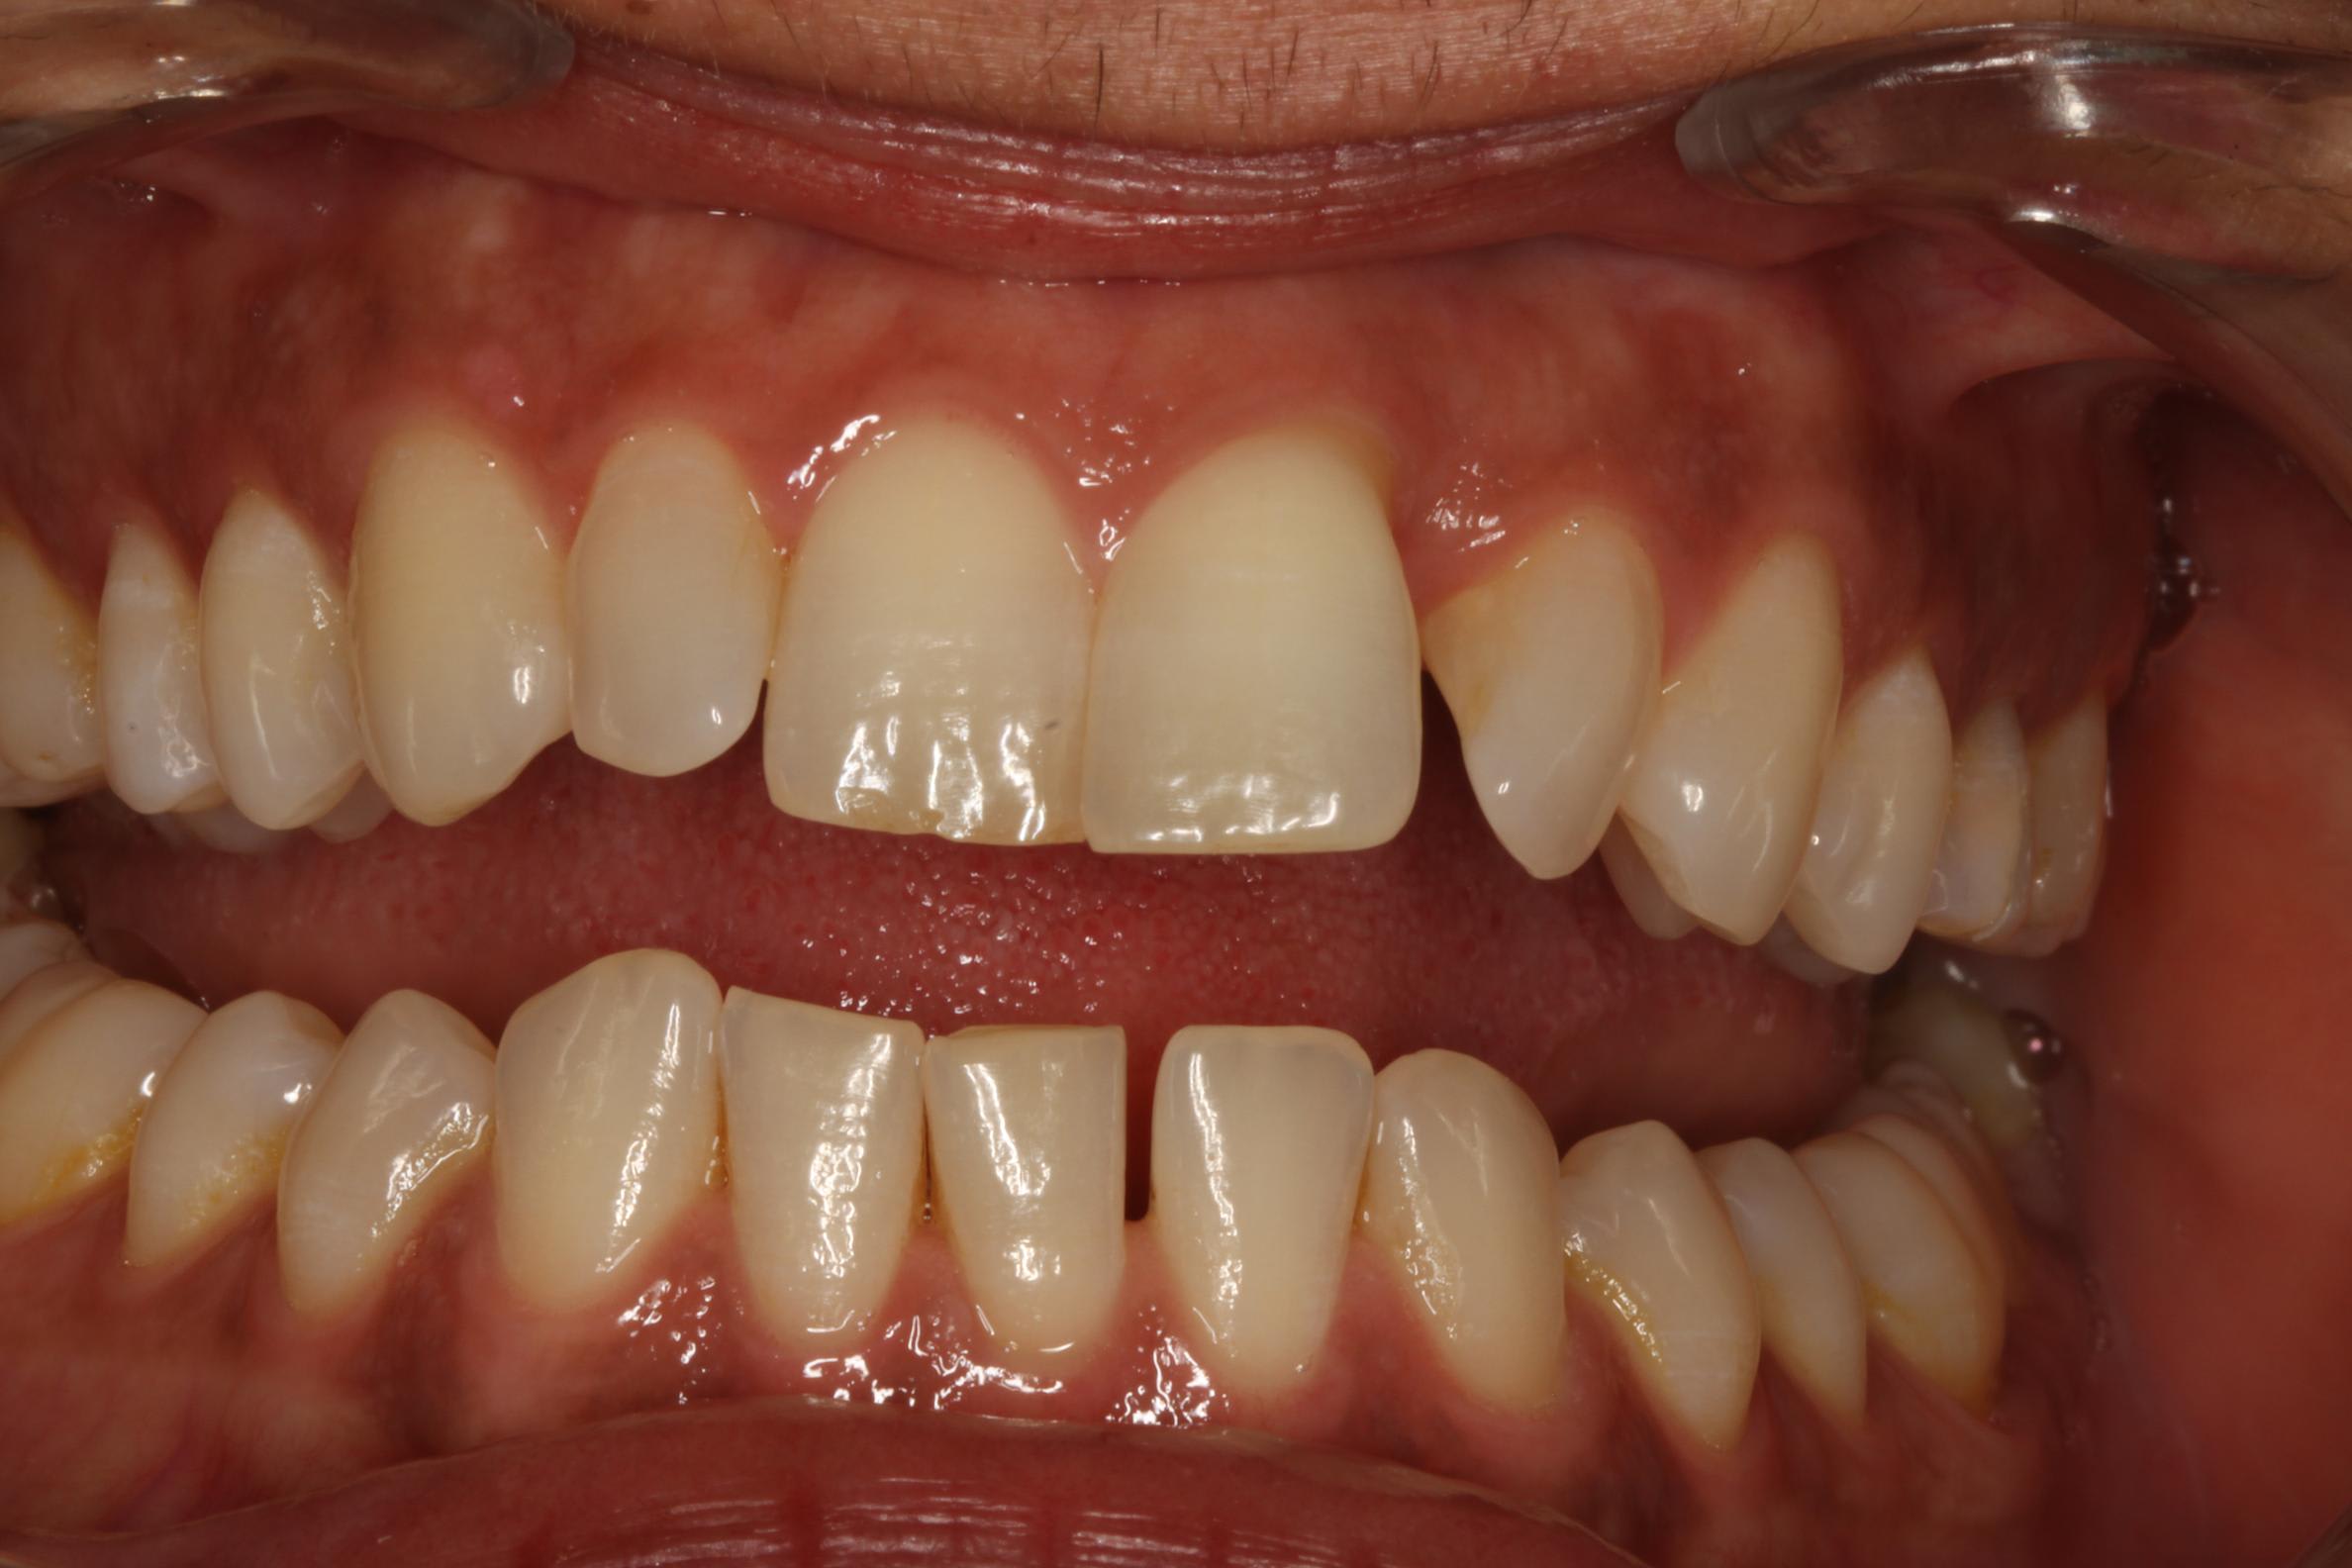

Que proposeriez vous à cette patiente de 40 ans dont la 21 s'est égressée...

Je la vois pour la 1ere fois, le sondage parodontal ne montre pas de poche parodontale (un long epithelium de jonction?)

pas de poche????

t'as vu la tronche de cette 21???

la courbe de Spee est prononcée, les incisives inf paraissent égressées et vestibulées, l'onde de choc masticatoire arrive à 90° sur les inc sup, la langue est ptêt basse. je commencerais par niveler et redresser les inc inf pour libérer les inc sup de toute la charge occlusale, puis rétablissement du guide incisif en redressant les inc sup

Le problème du cas de Dentheo33 peut avoir deux origines (en plus du problème inflammatoire paro passé ou présent) :

Un tic de pulsion linguale (peu probable), plutôt une mastication déséquilibrée qu'il faut traiter en parallèle.